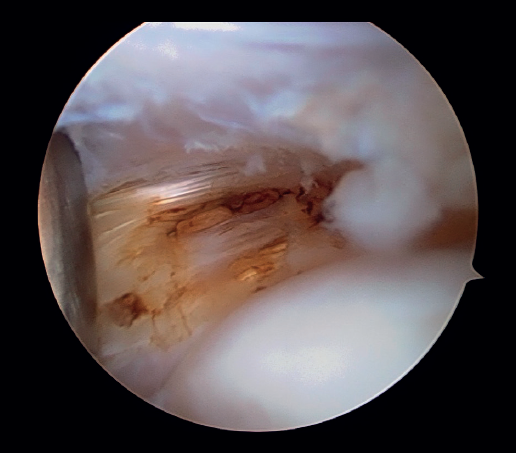

Posteriormente, se realiza la capsulotomía parcial lateral con sinoviotomo o vaporizador, hasta conseguir apreciar el ECRB (Figura 7). Una vez que se consigue su visualización, mediante el sinoviotomo y el vaporizador, se procede a la tenotomía de la inserción del ECRB en el epicóndilo, así como del tejido degenerativo tendinoso asociado (Figura 8). La liberación del tendón del ECRB debe limitarse a una zona anterior al eje central de la cabeza radial con el codo a 90°, para preservar la integridad del ligamento colateral lateral.

Figura 8. Tenotomía del extensor carpi radialis brevis con vaporizador (paciente en decúbito lateral, codo derecho, visión desde el portal medial).